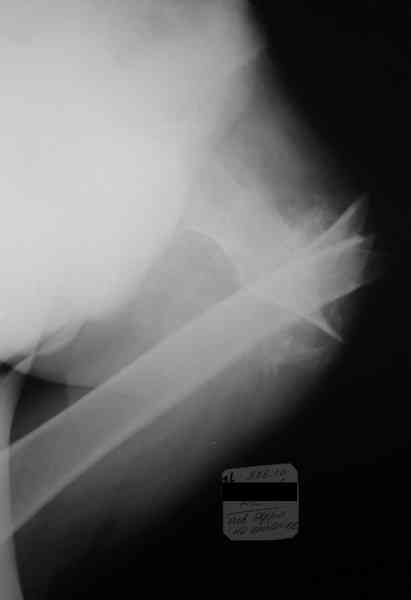

Неправильно консолидирующийся перелом бедра |

Уважаемые коллеги! Прошу помощи по приведенному случаю. Пациент 34 лет бомж получил травму окло 1,5-2 мес назад. За мед помощью не обращался. При поступлении левая нижняя конечность резко ротирована кнутри, варусная деформация бедра. По наружной поверхности рана 2 на 2 см с незначительным серозно гнойным отделяемым,умеренными грануляциями, в ране дистальный отломок бедреной кости. Патологическая подвижность в области перелома назначительная. Проведена попытка репозии дистракционным аппаратом, с незначительным эффектом (несколько уменьшилась внутренняя ротация.Что делать дальше? Остеотомия? Санация гнойного очага

Я бы начал с резекции мёртвой кости и хирургической обработки раны, поставил бы АВФ и цементные бусы с антибиотиками. После 6-ти недельного курса антибиотиков, фиксировал бы перелом штырём. Так как перелом весьма проксимальный (трудно судить по этому рентгену, надо сделать рентген с бедром на вытяжении), то есть вариант резекции прохимального отломка (Girdlestone arthroplasty). Нога укоротиться и пациент будет хромать, но будет ходить без болей. Но его можно будет мобилизировать довольно быстро, избегая проблемы с длительным постельным режимом и вытяжением. Учитывая, что больной вероятно не будет особо строго следовать указаниям врачей, это неплохой вариант для него и избежит осложнений с длительным лечением.

А ножка выглядит так (приложение).

Произведена секвестрэктомия, остеотомия костной мозоли(кстати говоря мозоль оказалась довольно таки приличной) Рана ушита нагрухо. Наложено ДСВ за мышелки бедра. Рана зажила первичным натяжением. Пациенту наложен коксит, готовится на выписку.